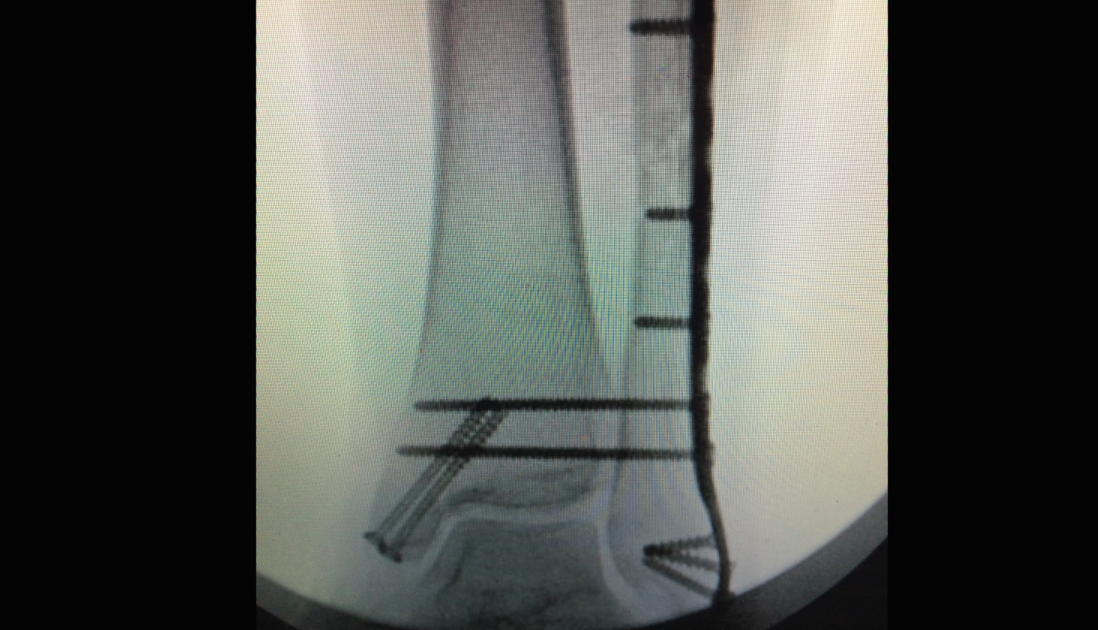

Ankle Fracture

Carbofix Ankle w VO April 2016 SS

Ankle Fx July 27 w VO

IFS Ankle Fx w VO

Sonoma Fibula Rod Jan 2016 w VO